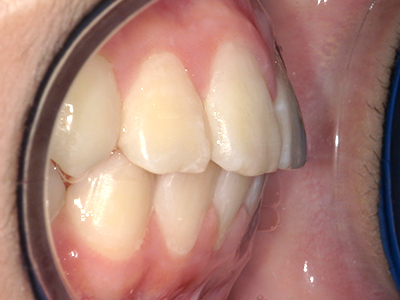

歯並びの相談に来られるお子様は、口呼吸をしているケースが多く、これが歯並びに大きな影響を与えています。

↓ - 上あごが狭くなる

↓ - 下あごが狭くなる・下あごの位置が悪くなる

↓ - さまざまな不正咬合が生じる

ないき歯科クリニックでは、上あごの成長不足を補い、鼻呼吸を獲得しつつ歯列を整え、将来のお口をより健康な状態にすることをゴールに定める矯正治療をおこなっています。